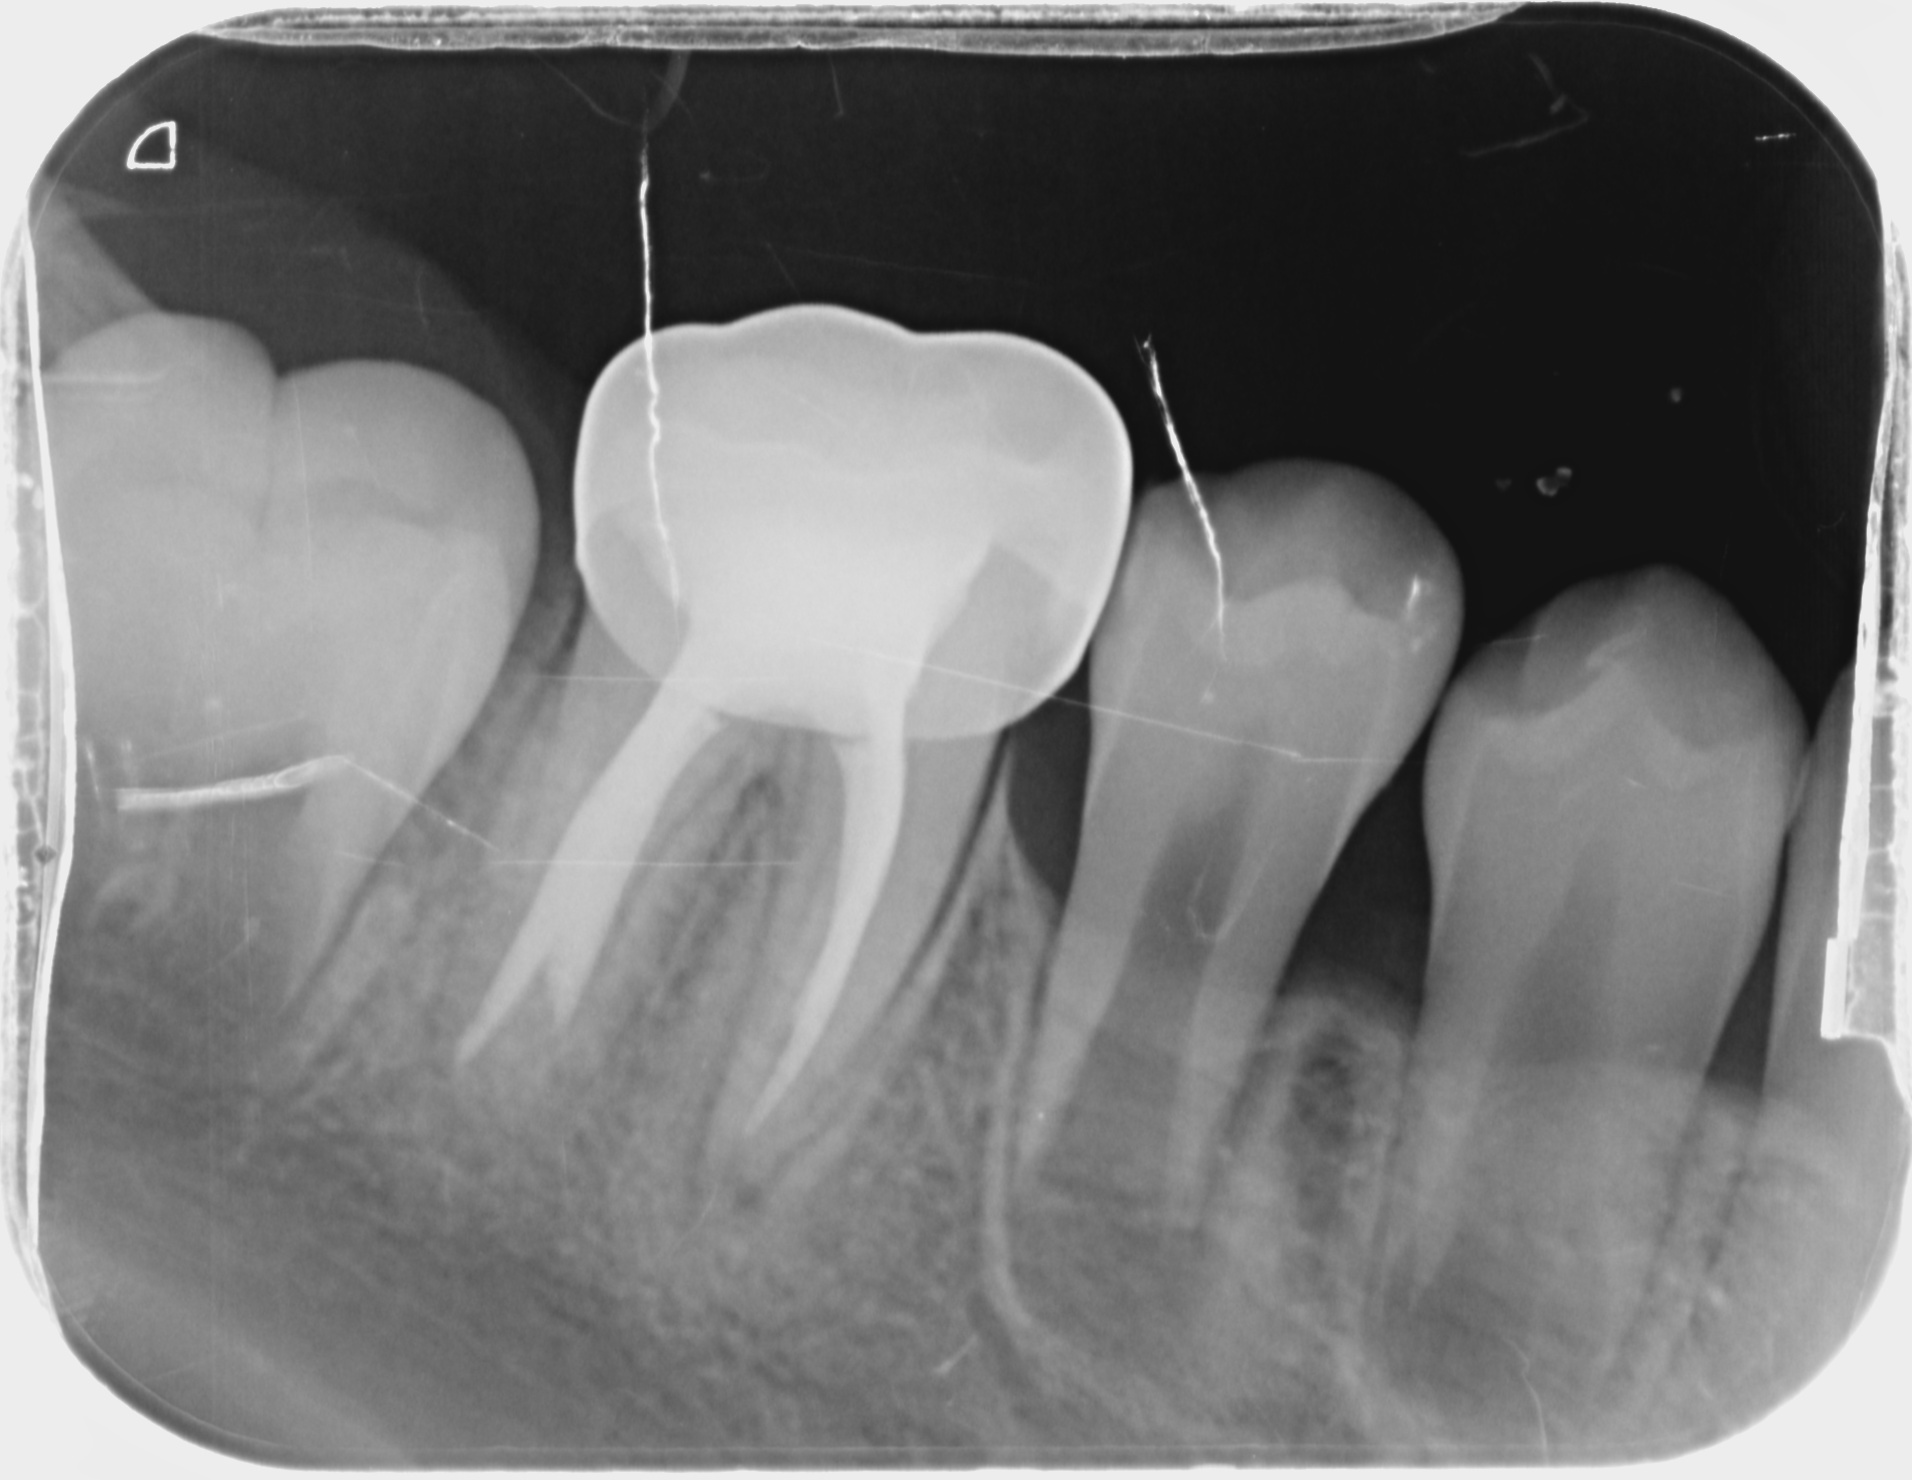

환아의 치료 전, 엑스레이와 구강 내 사진입니다. 거의 모든 치아에 충치가 있습니다. 특히 아래 어금니는 치아의 절반 넘게 충치로 깨져 없어진 상태입니다. 무서워서 빼야 할 시기를 한참 넘긴 남아있는 유치들도 많습니다. 그리고 영구치 윗니 앞니에 사이 충치가 보이네요.

치료 전. 치아의 반 넘게 충치로 깨져있습니다.